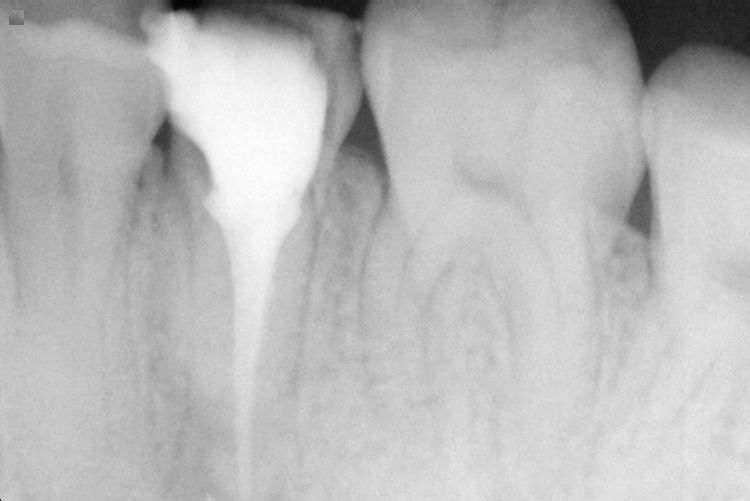

Name Last modified Size Description Parent Directory - IO000001.jpg 2020-07-28 14:17 78K IO000002.jpg 2020-07-28 14:17 78K IO000003.jpg 2020-07-28 14:17 81K IO000004.jpg 2020-07-28 14:17 76K